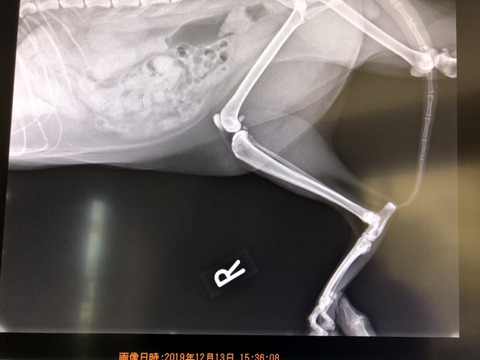

でも、微熱と言うか、40度ぐらいの熱が続くカカオは、若干、腹水もみられ、

最悪な事にFIPの診断が下されてしまいました。。。